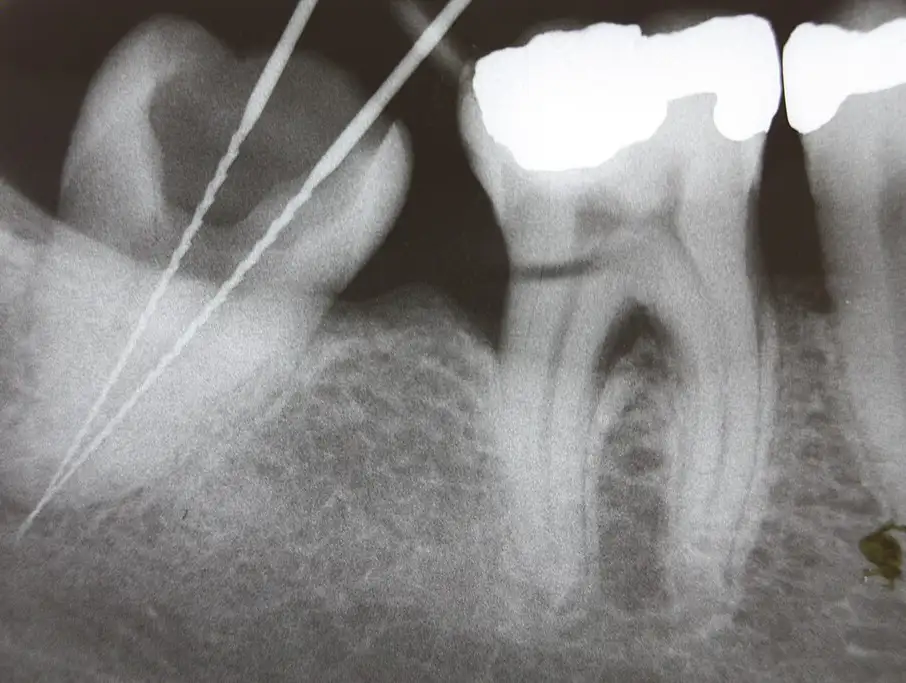

🔹 Evaluación y diagnóstico con radiografías digitales de alta precisión.